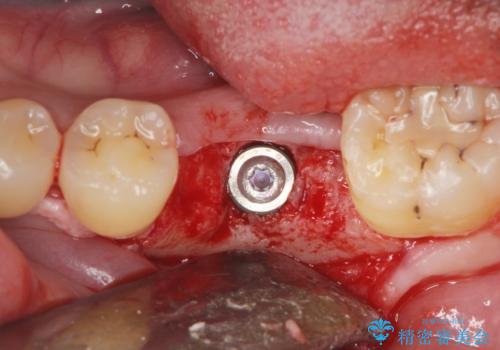

減ってしまった顎骨に増骨処置を行うことで、より安定した環境で長く使用できるようなインプラント治療を行っています。